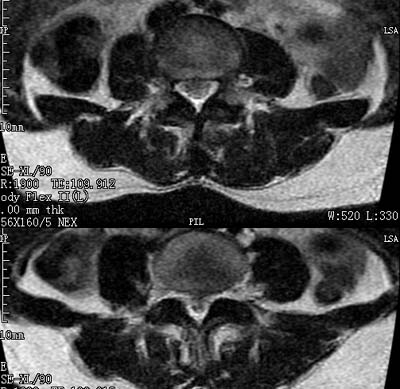

患者,女,50岁,左侧腹股沟及其下方疼痛、酸沉2年。

请各位战友看一下l4-5椎间盘后方椎管内是病灶吗?马尾神经到此处是不是终止了?

l4/5椎间盘突出。后方硬膜囊受压改变。另外,该病人是否并发子宫肌瘤啊

腰45椎间盘突出,马尾终丝聚集:考虑蛛网膜炎症粘连

l4-5轻突,黄韧带增厚,蛛网膜炎症粘连可能

l4/5椎间盘突出;马尾终丝聚集,考虑蛛网膜炎所致。